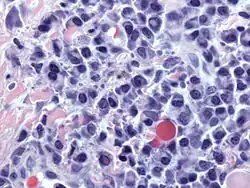

Micrograph of malignant plasma cells (plasmacytoma), many displaying characteristic "clockface nuclei", also seen in normal plasma cells. H&E stain. | |

Plasma cells are large lymphocytes with abundant cytoplasm and a characteristic appearance on light microscopy. They have basophilic cytoplasm and an eccentric nucleus with heterochromatin in a characteristic cartwheel or clock face arrangement. Their cytoplasm also contains a pale zone that on electron microscopy contains an extensive Golgi apparatus and centrioles. Abundant rough endoplasmic reticulum combined with a well-developed Golgi apparatus makes plasma cells well-suited for secreting immunoglobulins.[4] Other organelles in a plasma cell include ribosomes, lysosomes, mitochondria, and the plasma membrane.

Plasmacytoma, multiple myeloma, Waldenström macroglobulinemia, heavy chain disease, and plasma cell leukemia are cancers of the plasma cells.[33] Multiple myeloma is frequently identified because malignant plasma cells continue producing an antibody, which can be detected as a paraprotein. Monoclonal gammopathy of undetermined significance (MGUS) is a plasma cell dyscrasia characterized by the secretion of a myeloma protein into the blood and may lead to multiple myeloma.[34]